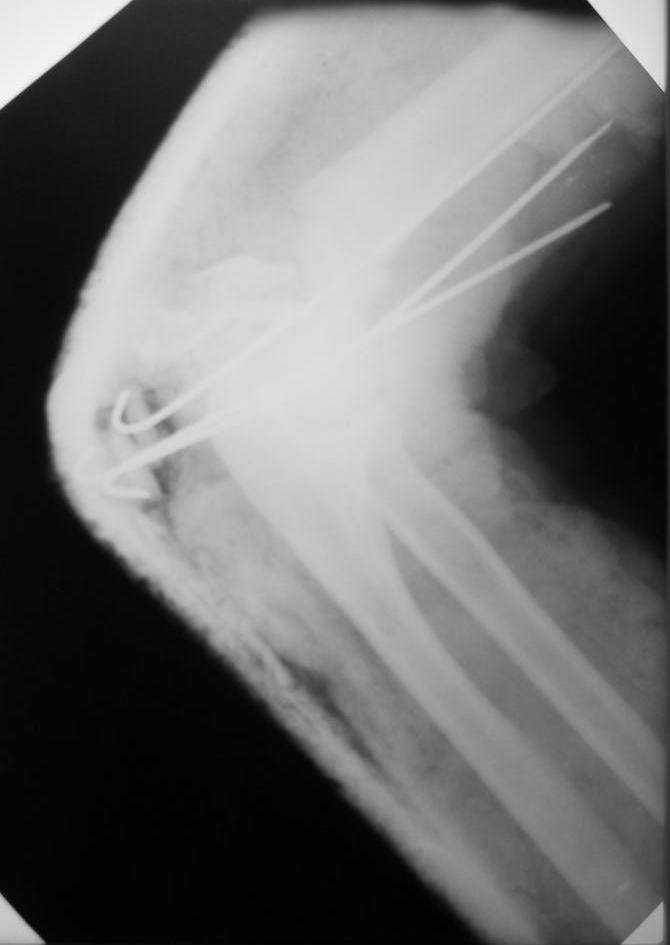

больная Ч. 24 года. Поступила в отделение после ДТП 15.01.08 при поступлении о/с костей таза АВФ. О/с лев плечевой кости спицами. На данный момент состояние больной ближе к удовлетворительному. С переломом костей голени особых вопросов нет. Хотелось бы услышать ваше мнение.

Где на этих снимках "о/с" плечевой кости?.

Какова была цель проведения спиц, даже, если бы они попали туда, куда было задумано?

Что имелось ввиду под "о/c лев. плечевой кости"?

Если насчет дистального перелома плеча, из-за отсутствия прямых снимков, невозможно определить состояние мышелков. Очень редко случается перелом одного мыщелка, обычно Т-или Y образные переломы мыщелков. Сопоставление trochlea в сустав не решает главную проблему, спицы прошли мимо основных несопоставленных фрагментов.

Адекватный доступ получается с остеотомией локтевого отростка. Сопоставленные мышелки, фиксируют двойной пластиной и возможно межфрагментарные шурупы на мыщелки. Только таким образом можно соединить дистальное плечо с диафизом.

Спицы удалить за ненадобностью и сделать снимок локтевого сустава в передне-задней и боковой проекциях без гипса.

насколько учили меня- основной принцип медицины- не навреди. данный "остеосинтез" кроме вреда ничего не сулит. Уточните неврологическую симптоматику до и после операции. удалите спицы.

Если не планируете оперировать в ближайшее время- спицу через локтевой отросток и вытяжение либо на отводящее шине, либо кверху на балканской раме.